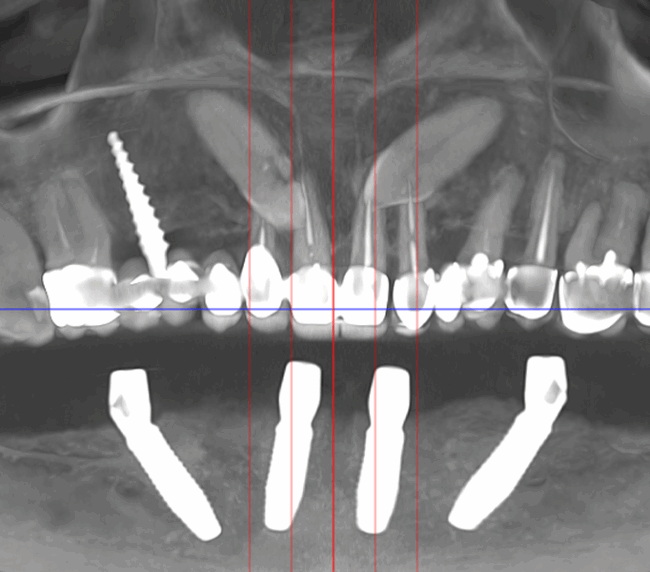

studii științifice.În cazurile de atrofie osoasă severă, când inserarea implanturilor în zonele laterale nu este posibilă fără adăugare osoasă, conceptul All-on-4 prevede plasarea implanturilor în unghiuri strategice pentru a evita zonele deficitare. Astfel, două implanturi sunt plasate în zona incisivilor laterali, iar alte două în zona premolarilor.

- Investigație imagistică completă, ideal CBCT (computer tomografie);

- Planificare computerizată a intervenției și, dacă este necesar, realizarea ghidului chirurgical;